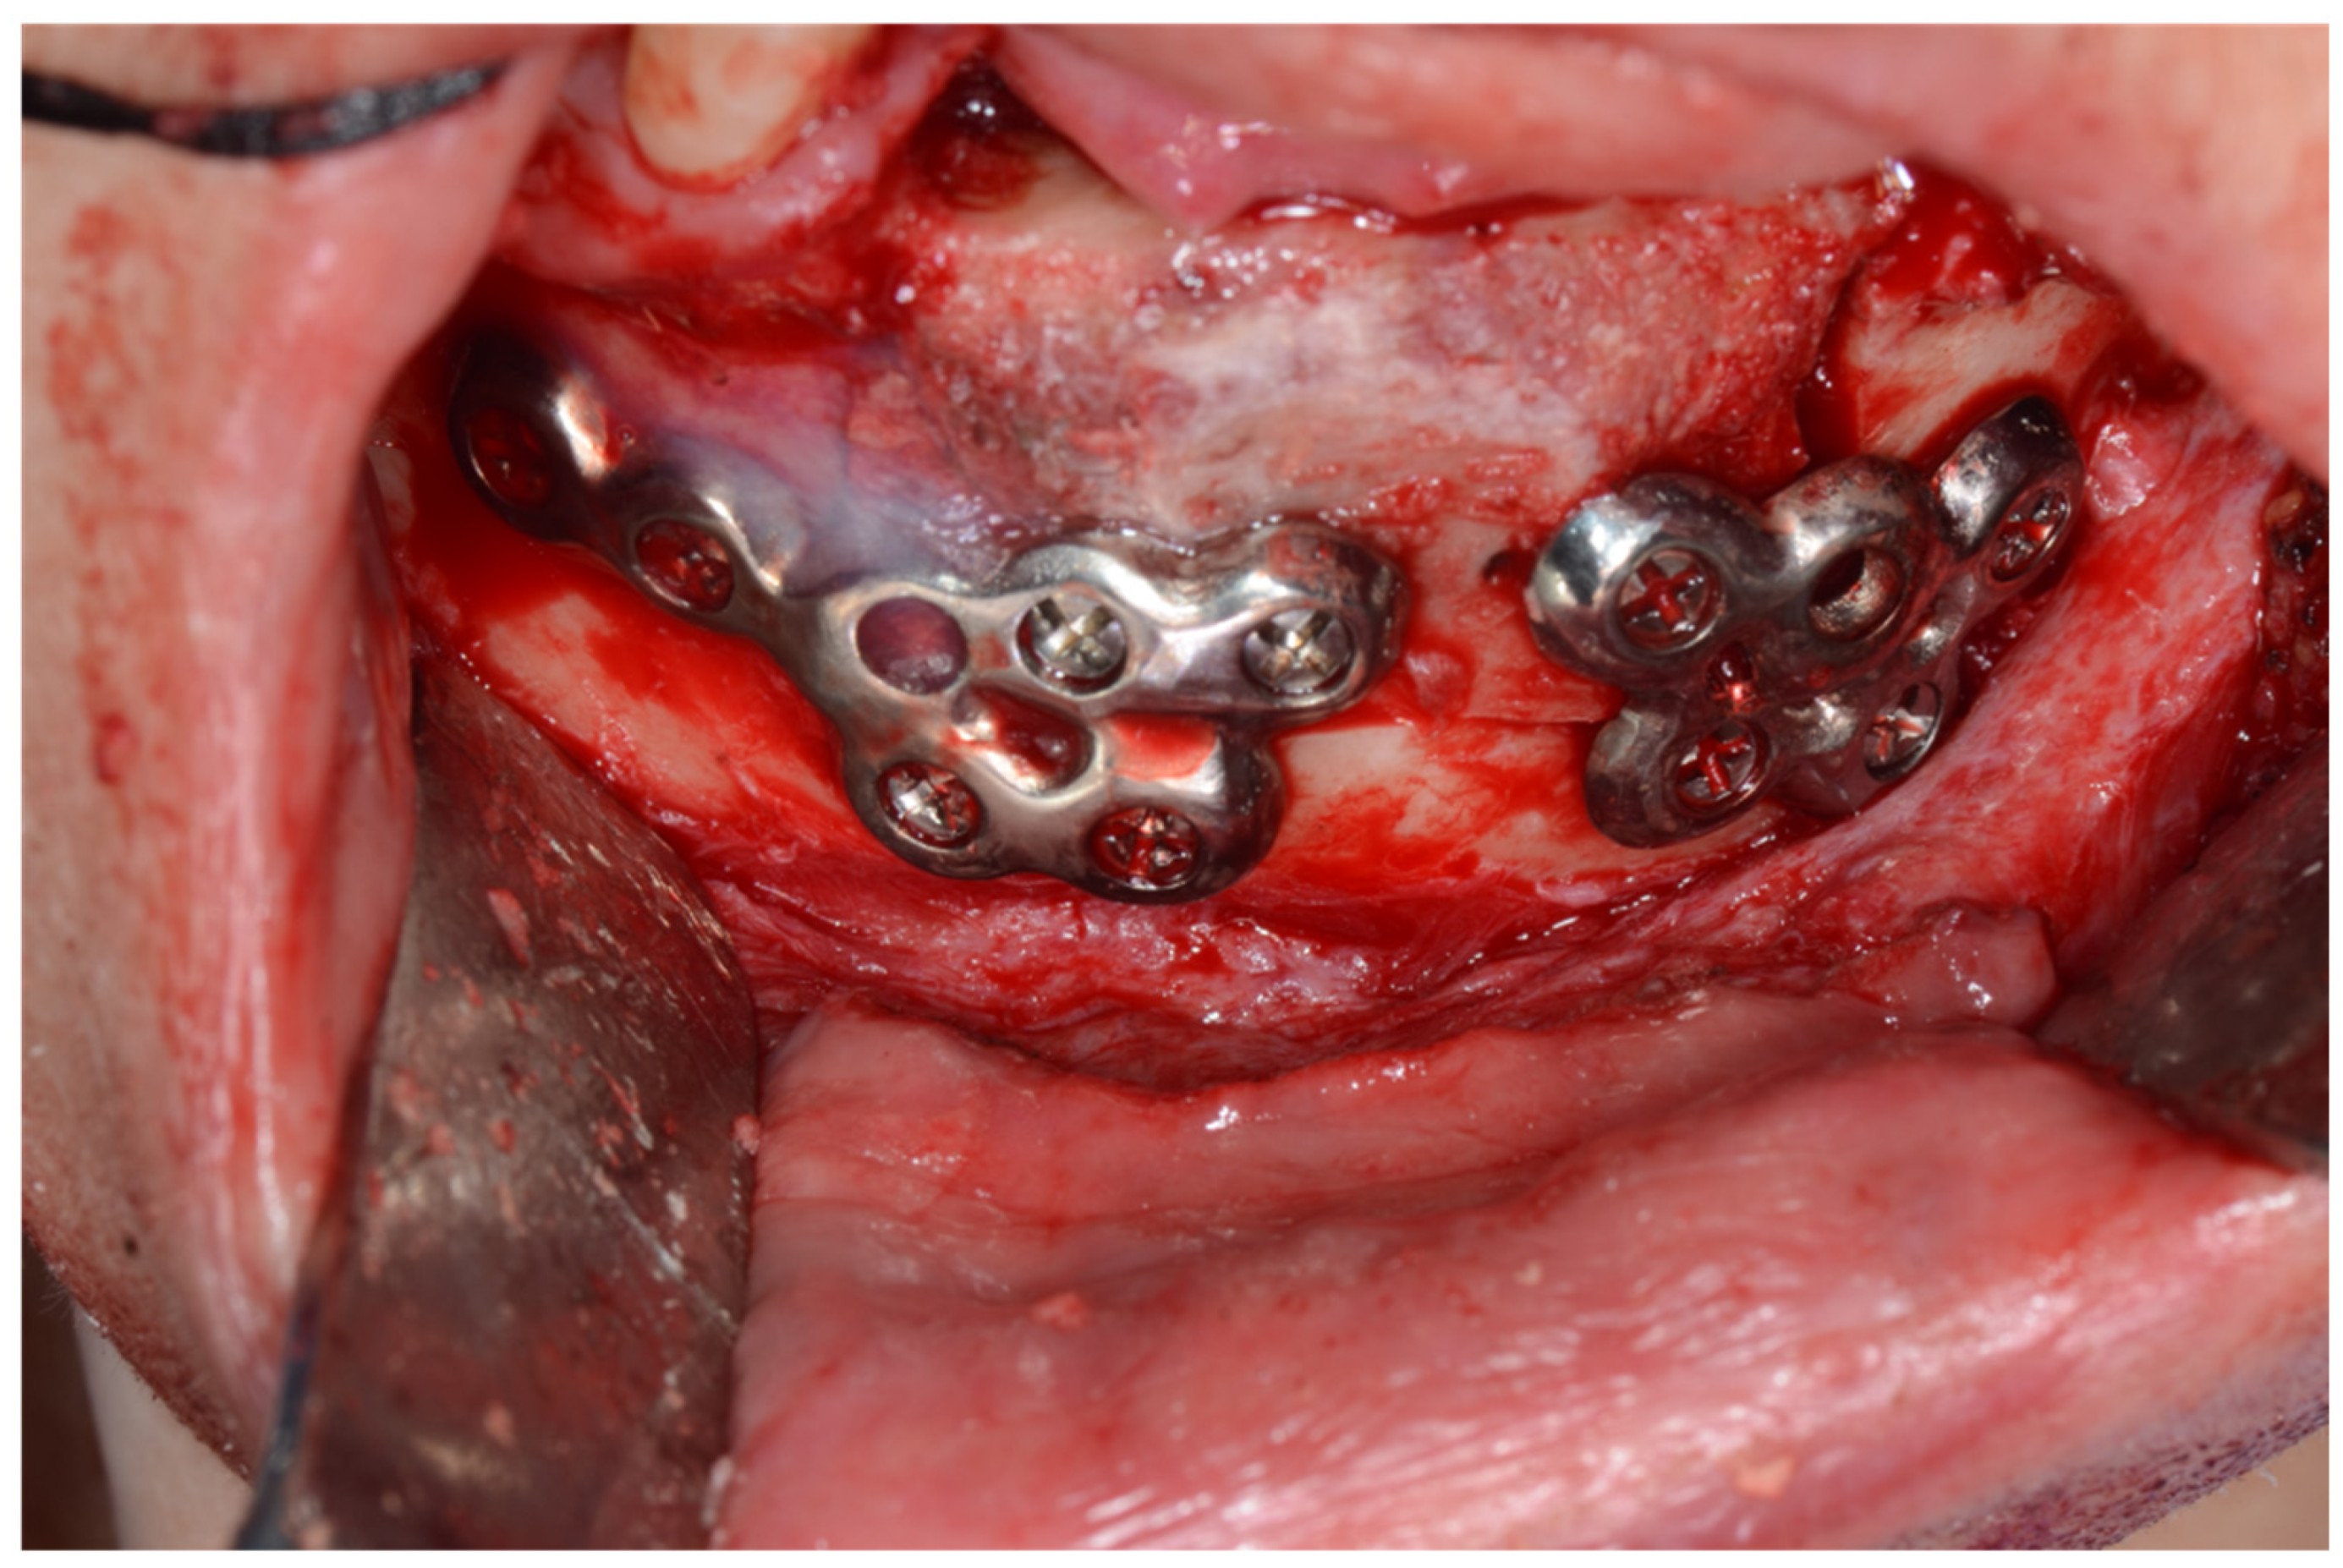

A 31-year-old male patient who underwent segmental mandibulectomy and DCIA iliac crestal free-flap reconstruction for a mandibular defect presented with plate exposure and non-union at the reconstruction site due to the infection of the reconstruction site (Figure 1).

Surgical guides and customized plates were manufactured according to the preoperative plan, and the reconstruction was performed using these surgical guides and customized plates (Figure 4 and Figure 5).

Figure 5. Intraoperative photo: (a) application of iliac bone guide; (b) mandible reconstruction with customized plate; (c) donor site reconstruction with titanium mesh and allobone chip graft (ReadiGRAFT Cancellous Chips; LifeNet Health, Virginia Beach, VA, USA); (d) application of fibrin glue (Greenplast; Green Cross, Yongin, Republic of Korea) after suturing using the internal oblique muscle flap.